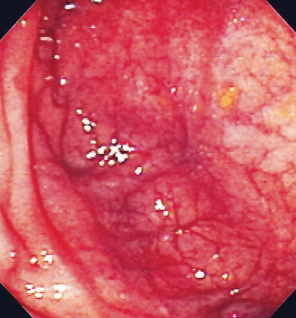

Κολονοσκόπηση. Ευδιάκριτα ευρήματα ισχαιμικής κολίτιδας (Ευγενική παραχώρηση Dr. V. Penopoulos)